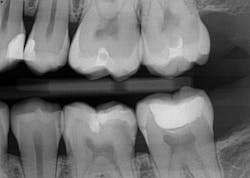

Caries lesions were removed and air abrasion was employed to remove impurities on the unprepared tooth surfaces and create increased surface area for bonding. Preparation of the class II carious lesions revealed demineralization on the adjacent tooth structure (figure 3). When lesions such as these are discovered, dentists are often at a crossroads whether to intervene or monitor the area for progression. It is my experience that these early caries lesions can be predictably arrested with resin infiltration (figure 4), and that no intervention usually results in the progression of caries.

In this case, lateral access was achieved by the preparation of the adjacent teeth as part of the proposed treatment plan. Early caries lesions that are noted on radiographs that are not accessible in cases such as this one can be accessed by placing an orthodontic spacer. This patient was restored with direct composite bonding (figure 5) and these restorations have proven to have a favorable long-term outcome (figure 6).